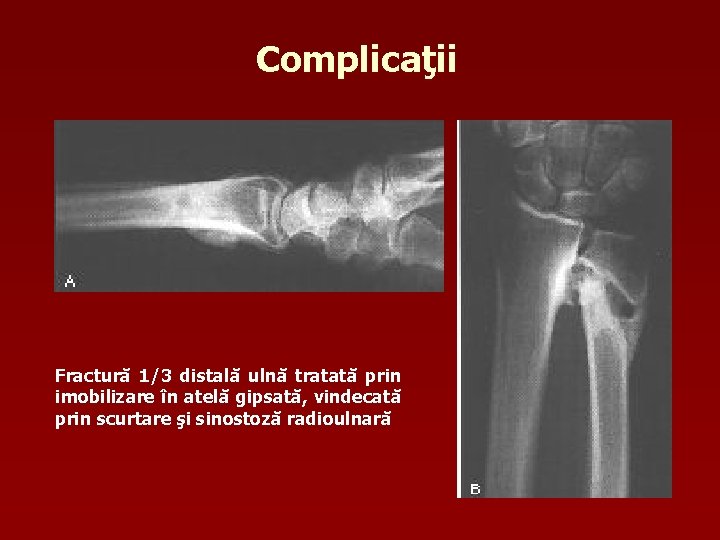

Complicaţii Imediate n Fractura deschisă n Leziuni vasculo-nervoase n Sindrom Volkmann (sindrom de lojă anterioară) Tardive n Calusul vicios (cu decalaj, unghiulare, sinostoză radiocubitală) Pseudartroza n Sindromul de retracţie tendino -musculară ischemică n

Complicaţii Fractură 1/3 distală ulnă tratată prin imobilizare în atelă gipsată, vindecată prin scurtare şi sinostoză radioulnară